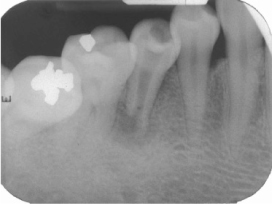

Figure 1

Periapical view: pre-operative radiograph.

Figure 1 Periapical view: pre-operative radiograph.